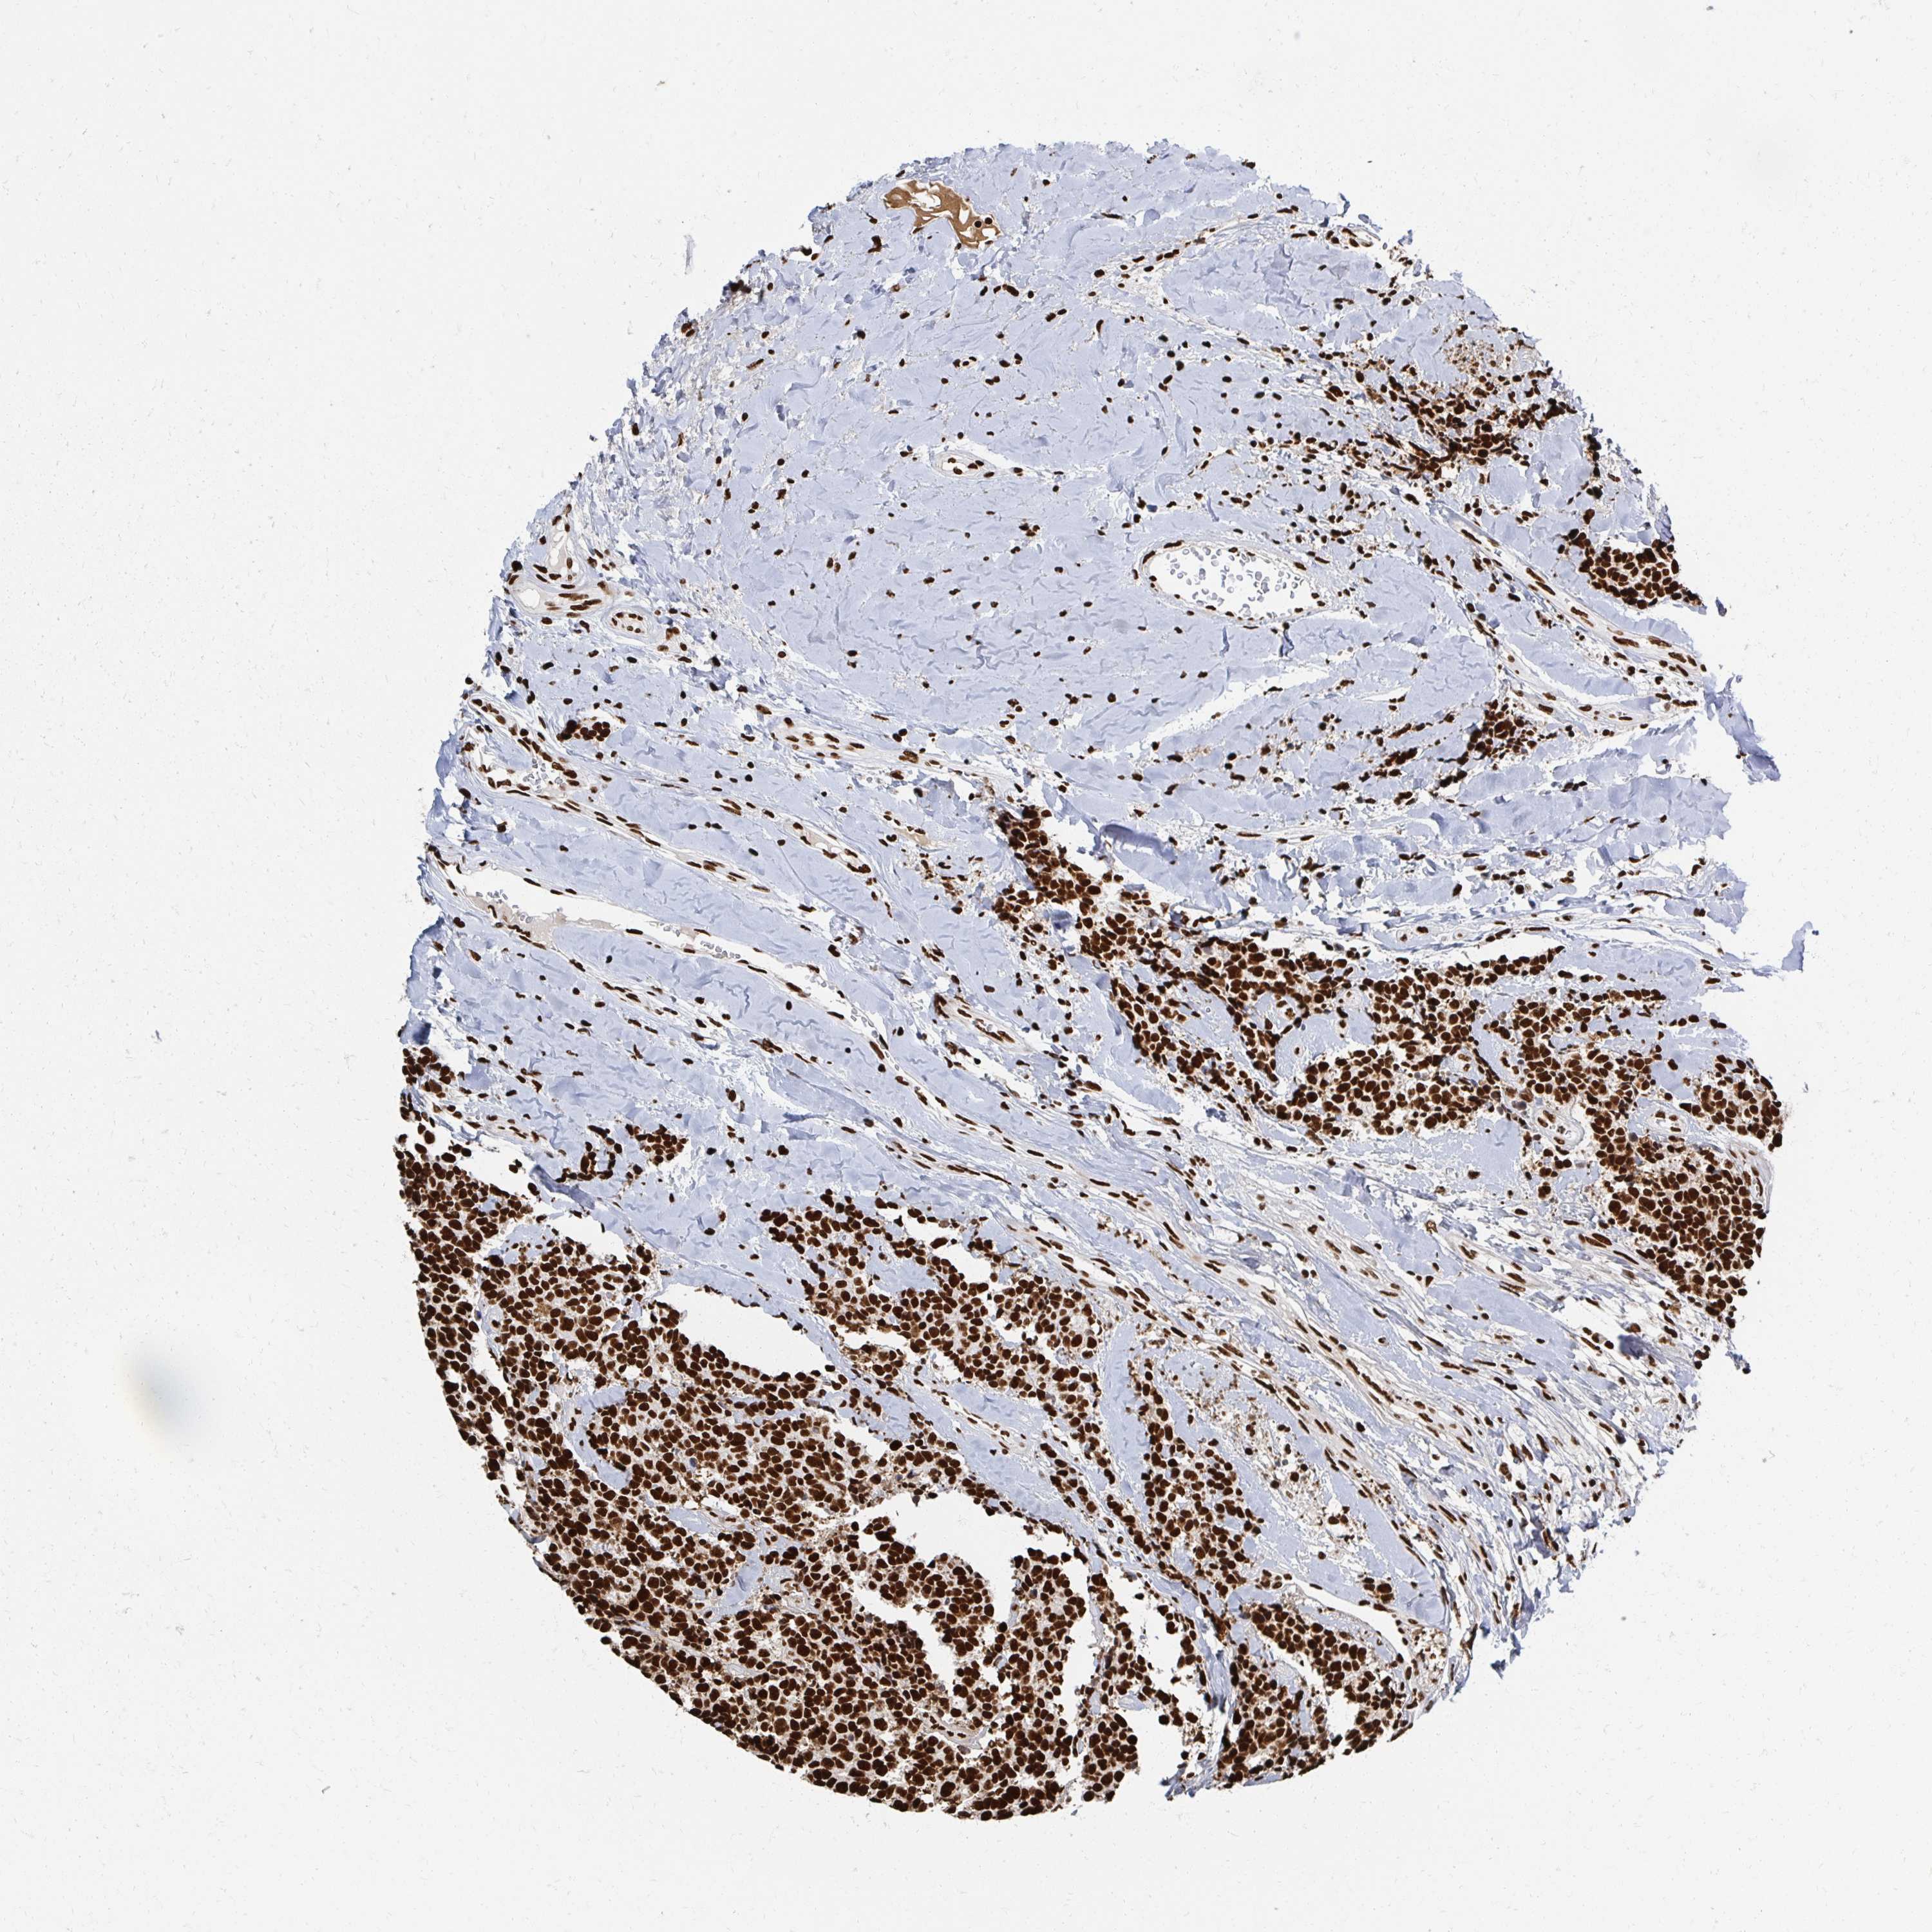

RBBP4